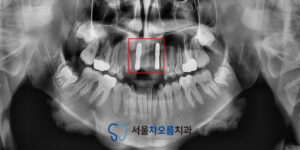

25.05.09

이렇게 식립 후 임플란트의 치유기간을 거친 뒤

보철 작업을 시작하였습니다.

앞니 부분이다 보니

심미적인 요소가 중요하기 때문에,

치아의 색상, 모양, 크기 등을

세심하게 고려하여

보철물을 제작하였습니다.

환자분과 함께 확인해보면서

보철물을 조정한 뒤,

괜찮으시다고 하셔서

영구접착을 진행하였습니다.